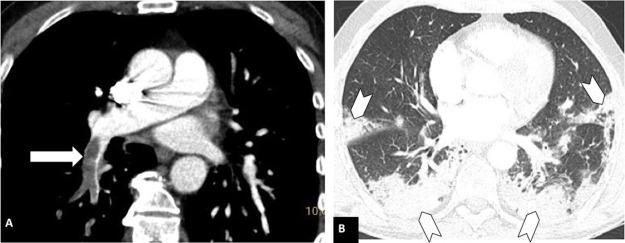

To determine the prevalence of pulmonary embolism in patients with COVID-19; to determine the possible relationship between the severity of pulmonary involvement and D-dimer levels; to analyze the location of pulmonary embolisms in patients with COVID-19 and to compare it with the location in patients without COVID-19.

We included 492 pulmonary CT angiograms (342 (69.9%) in patients with COVID-19 and 147 (30.1%) in patients without COVID-19). The prevalence of pulmonary embolisms was higher in patients with COVID-19 (26% vs. 16.3% in patients without COVID-19, p=0.0197; relative risk=1.6). The prevalence of pulmonary embolisms in the same period in 2019 was 13.2%, similar to that of the group of COVID-19-negative patients in 2020 (p=0.43). There were no significant differences in D-dimer levels or the location of pulmonary embolisms between the two groups. CT showed moderate or severe pulmonary involvement in 78.7% of the patients with COVID-19.

确定 COVID-19 患者中肺栓塞的患病率;确定肺受累严重程度与 D-二聚体水平之间的可能关系;分析 COVID-19 患者肺栓塞的位置,并与无 COVID-19 患者的位置进行比较。

共纳入 492 例肺动脉 CT 血管造影(COVID-19 患者 342 例[69.9%],无 COVID-19 患者 147 例[30.1%])。COVID-19 患者肺栓塞的患病率较高(26%比无 COVID-19 患者[16.3%],p=0.0197;相对风险=1.6)。2019 年同期的肺栓塞患病率为 13.2%,与 2020 年无 COVID-19 患者组相似(p=0.43)。两组患者的 D-二聚体水平或肺栓塞位置无显著差异。CT 显示 COVID-19 患者中有 78.7%存在中度或重度肺受累。